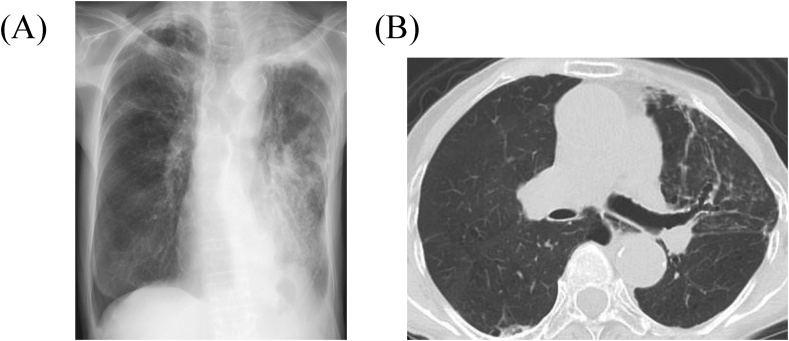

The patient was treated with an expectorant agent, bromhexine 8 mg three times daily, after the bronchoscopy. Three weeks later, chest radiographic findings revealed improvement of the collapsed left lung (Fig. 4A). Two months later, while she was completely recuperating from wet cough and breathing difficulty, SpO2 increased to 97% at room air and chest CT showed complete recovery of the collapsed lung, but with central bronchiectasis seen (Fig. 4B). Subsequently, she has returned to the clinic for follow-up and has continued bromhexine treatment successfully for more than 20 months. There were no adverse effects of bromhexine.

Fig. 4.

(A) Chest radiograph three weeks after initiation of bromhexine treatment shows improvement of the collapsed lung. (B) Chest computed tomography two months after initiation of bromhexine treatment shows central bronchiectasis and recovery of the collapsed lung.